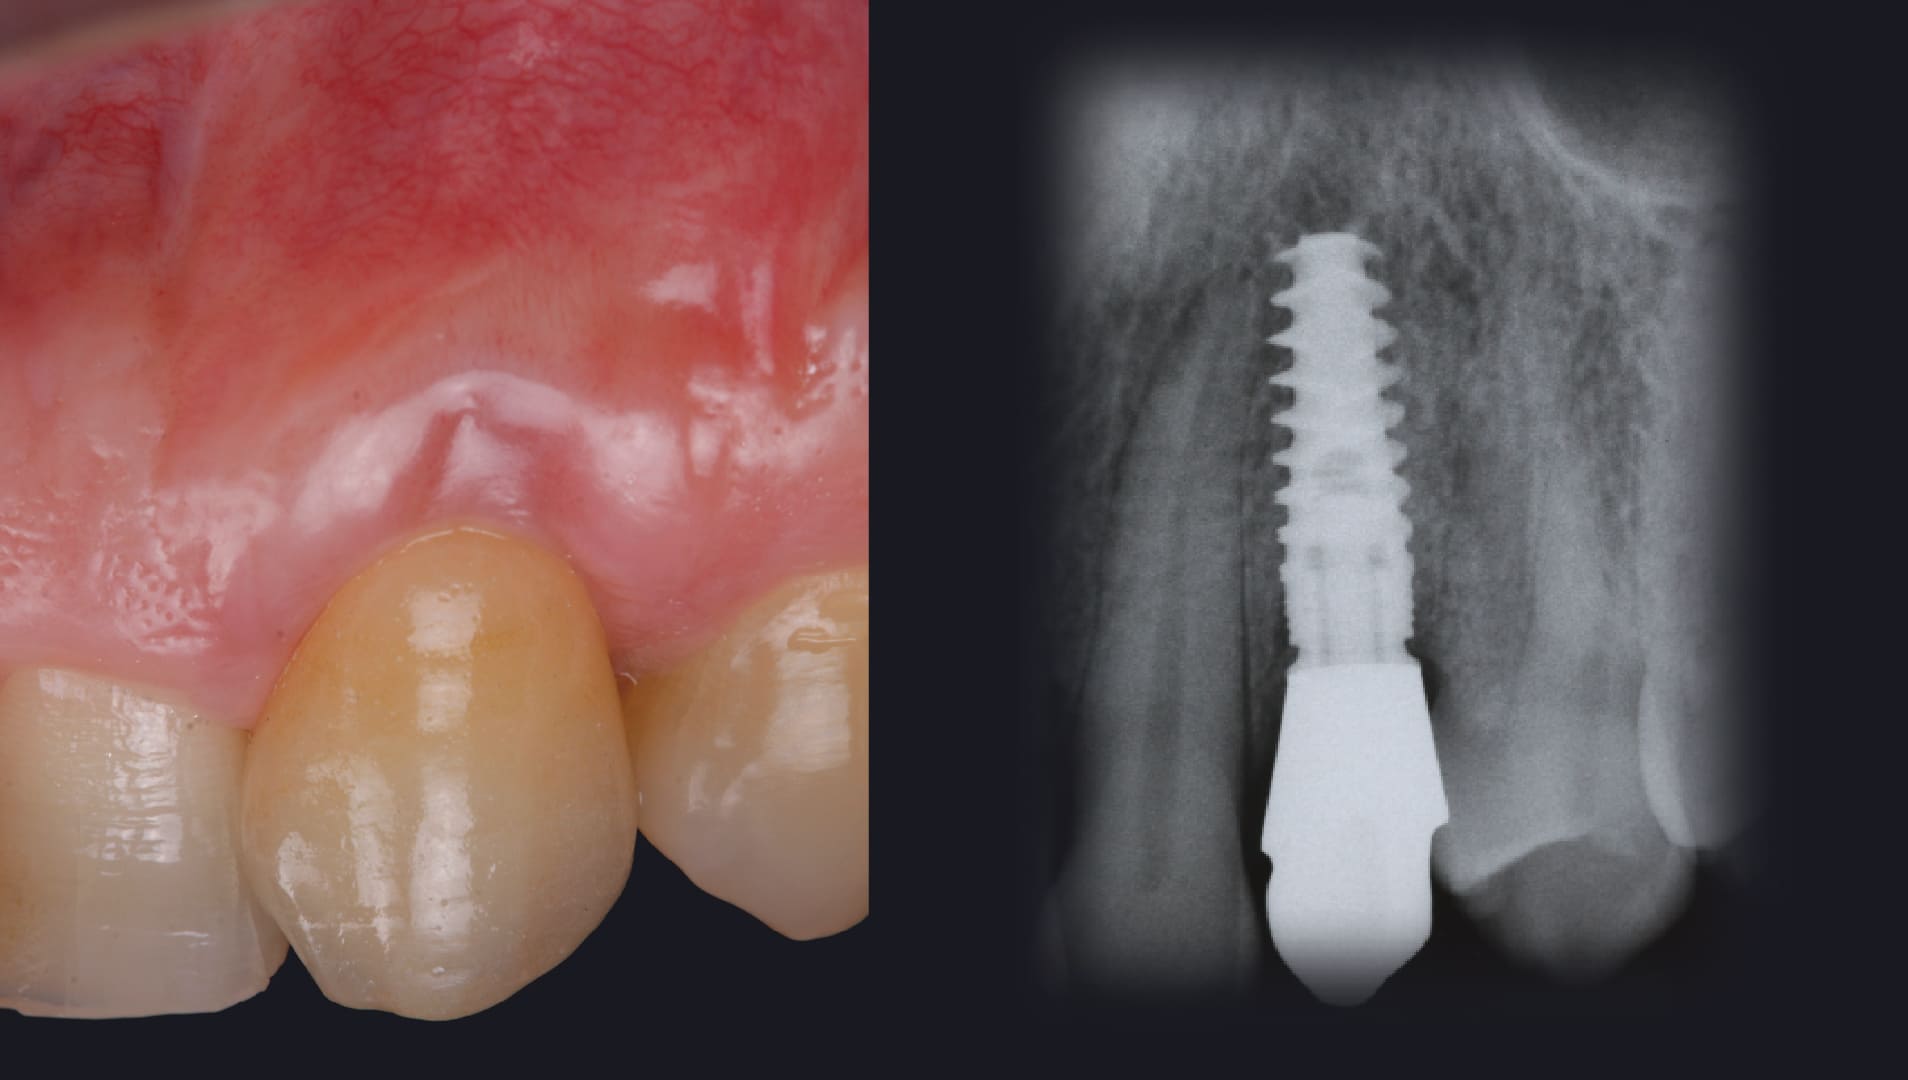

Immediate implant placement

Socket reconstruction with biomaterials and CTG

Management of the immediate provisional restorations contour

CLINICAL CASES